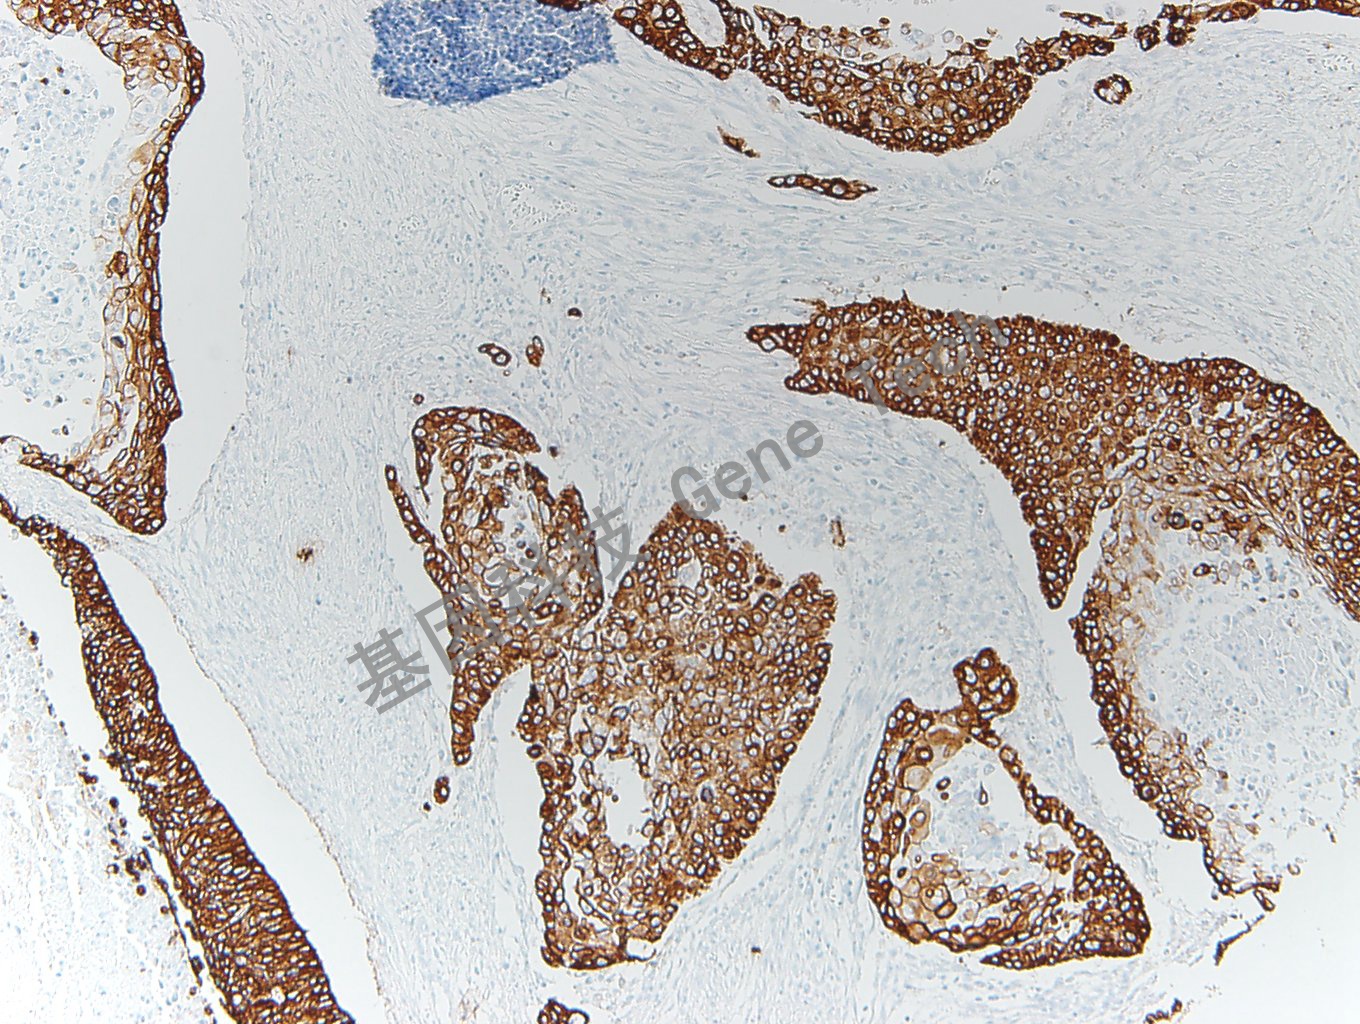

在正常的组织中,CK5 表达于鳞状上皮和导管上皮的基底细胞以及部分的鳞状上皮生发层细胞、肌上皮细胞和间皮细胞中,而绝大多数腺上皮细胞几乎不表达。CK5 可用于鳞癌和腺癌、间皮瘤和腺癌的鉴别诊断。亦可用于乳腺、涎腺、前列腺上皮来源肿瘤良、恶性的鉴别诊断。

【阳性部位】细胞浆

正常前列腺石蜡切片,用 CK5(GT2152)染色,细胞浆阳性,DAB 显色。